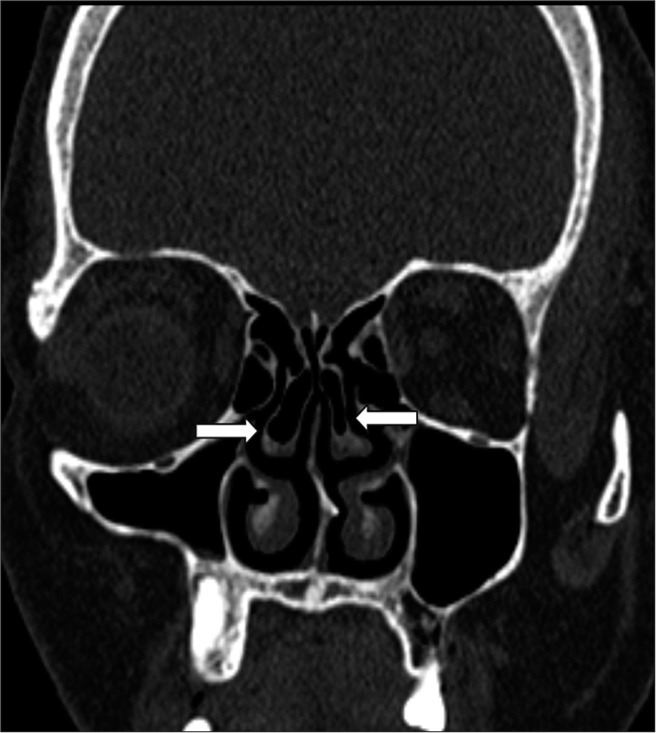

Material and methods: A case-control study was conducted with 103 patients presenting with chronic sinonasal symptoms (cases) and 50 asymptomatic individuals (controls). A 128-slice computed tomography scanner was used to measure maxillary sinus volume and assess anatomical variants, such as a deviated nasal septum (DNS), concha bullosa (CB), and agger nasi cells. Exclusion criteria included previous sinonasal surgery, malignancy, craniofacial trauma, and lack of consent. Statistical analysis was performed using t-tests for continuous variables and Chi-square tests for categorical data. Receiver operating characteristic curve analysis was utilized to determine a DNS angle cutoff for predicting CRS.

Results: Anatomical variants were significantly more frequent in cases than in controls. The left-sided DNS was predominant in cases, while the right-sided DNS was more common in controls. The mean DNS deviation angle was notably larger in cases (10.84° ± 7.87) than in controls (5.55° ± 5.02). Maxillary sinus volume was significantly smaller in cases (9.69 cc on the left side and 10.23 cc on the right side) compared to controls (18.57 cc and 18.46 cc, respectively), with female patients exhibiting smaller volumes than males. Agger nasi cells were detected in 51.5% of cases versus 8.0% of controls. A strong association was found between CB and contralateral DNS. The optimal DNS deviation angle cutoff for predicting CRS was identified as 12.7°.